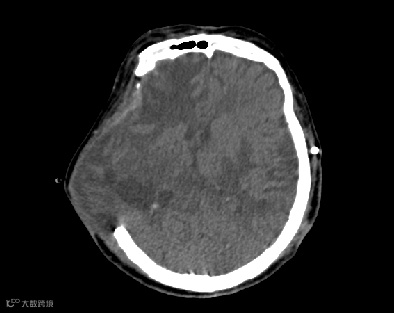

患者,女,66岁,右侧颅骨缺损

患者脑CT检查